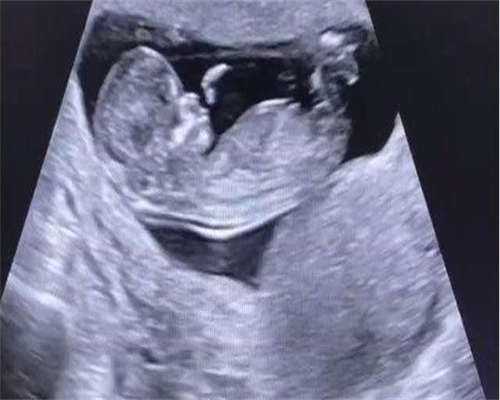

普遍应用PGD/PGS等先进技术,可有效预防染色体变异,还可对125种遗传性疾病筛查

单身冻卵、夫妻试管,第三代试管杜绝遗传疾病、遗传基因筛查等。

我们的医务团队非常重视每位客人的感受,从起初的首诊,到B超、回诊、取卵手术等全程尽力参与,坚持一患一医、拒绝流水线。